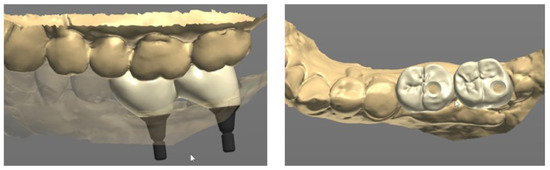

The final prosthesis was designed on a CAD software program through using the scanned information (Figure 4). The prefabricated link with appropriate height and diameter was selected considering the positional relationship between the implant and adjacent teeth and opposing teeth.

Next, the same laboratory process described in case 1 was performed. The prosthesis was designed on the CAD software, and a prefabricated link was selected through the scan data obtained from the model scan (Figure 10). A final prosthesis was obtained by milling zirconia through a CAM milling machine. A prefabricated substructure (link) (Toplan Co., Seoul, Republic of Korea) was fitted to the final prosthesis through frictional force.

Figure 4. Prosthetic design of implant prosthesis on CAD software program.

Figure 10. Prosthetic design of implant prosthesis on CAD software program.